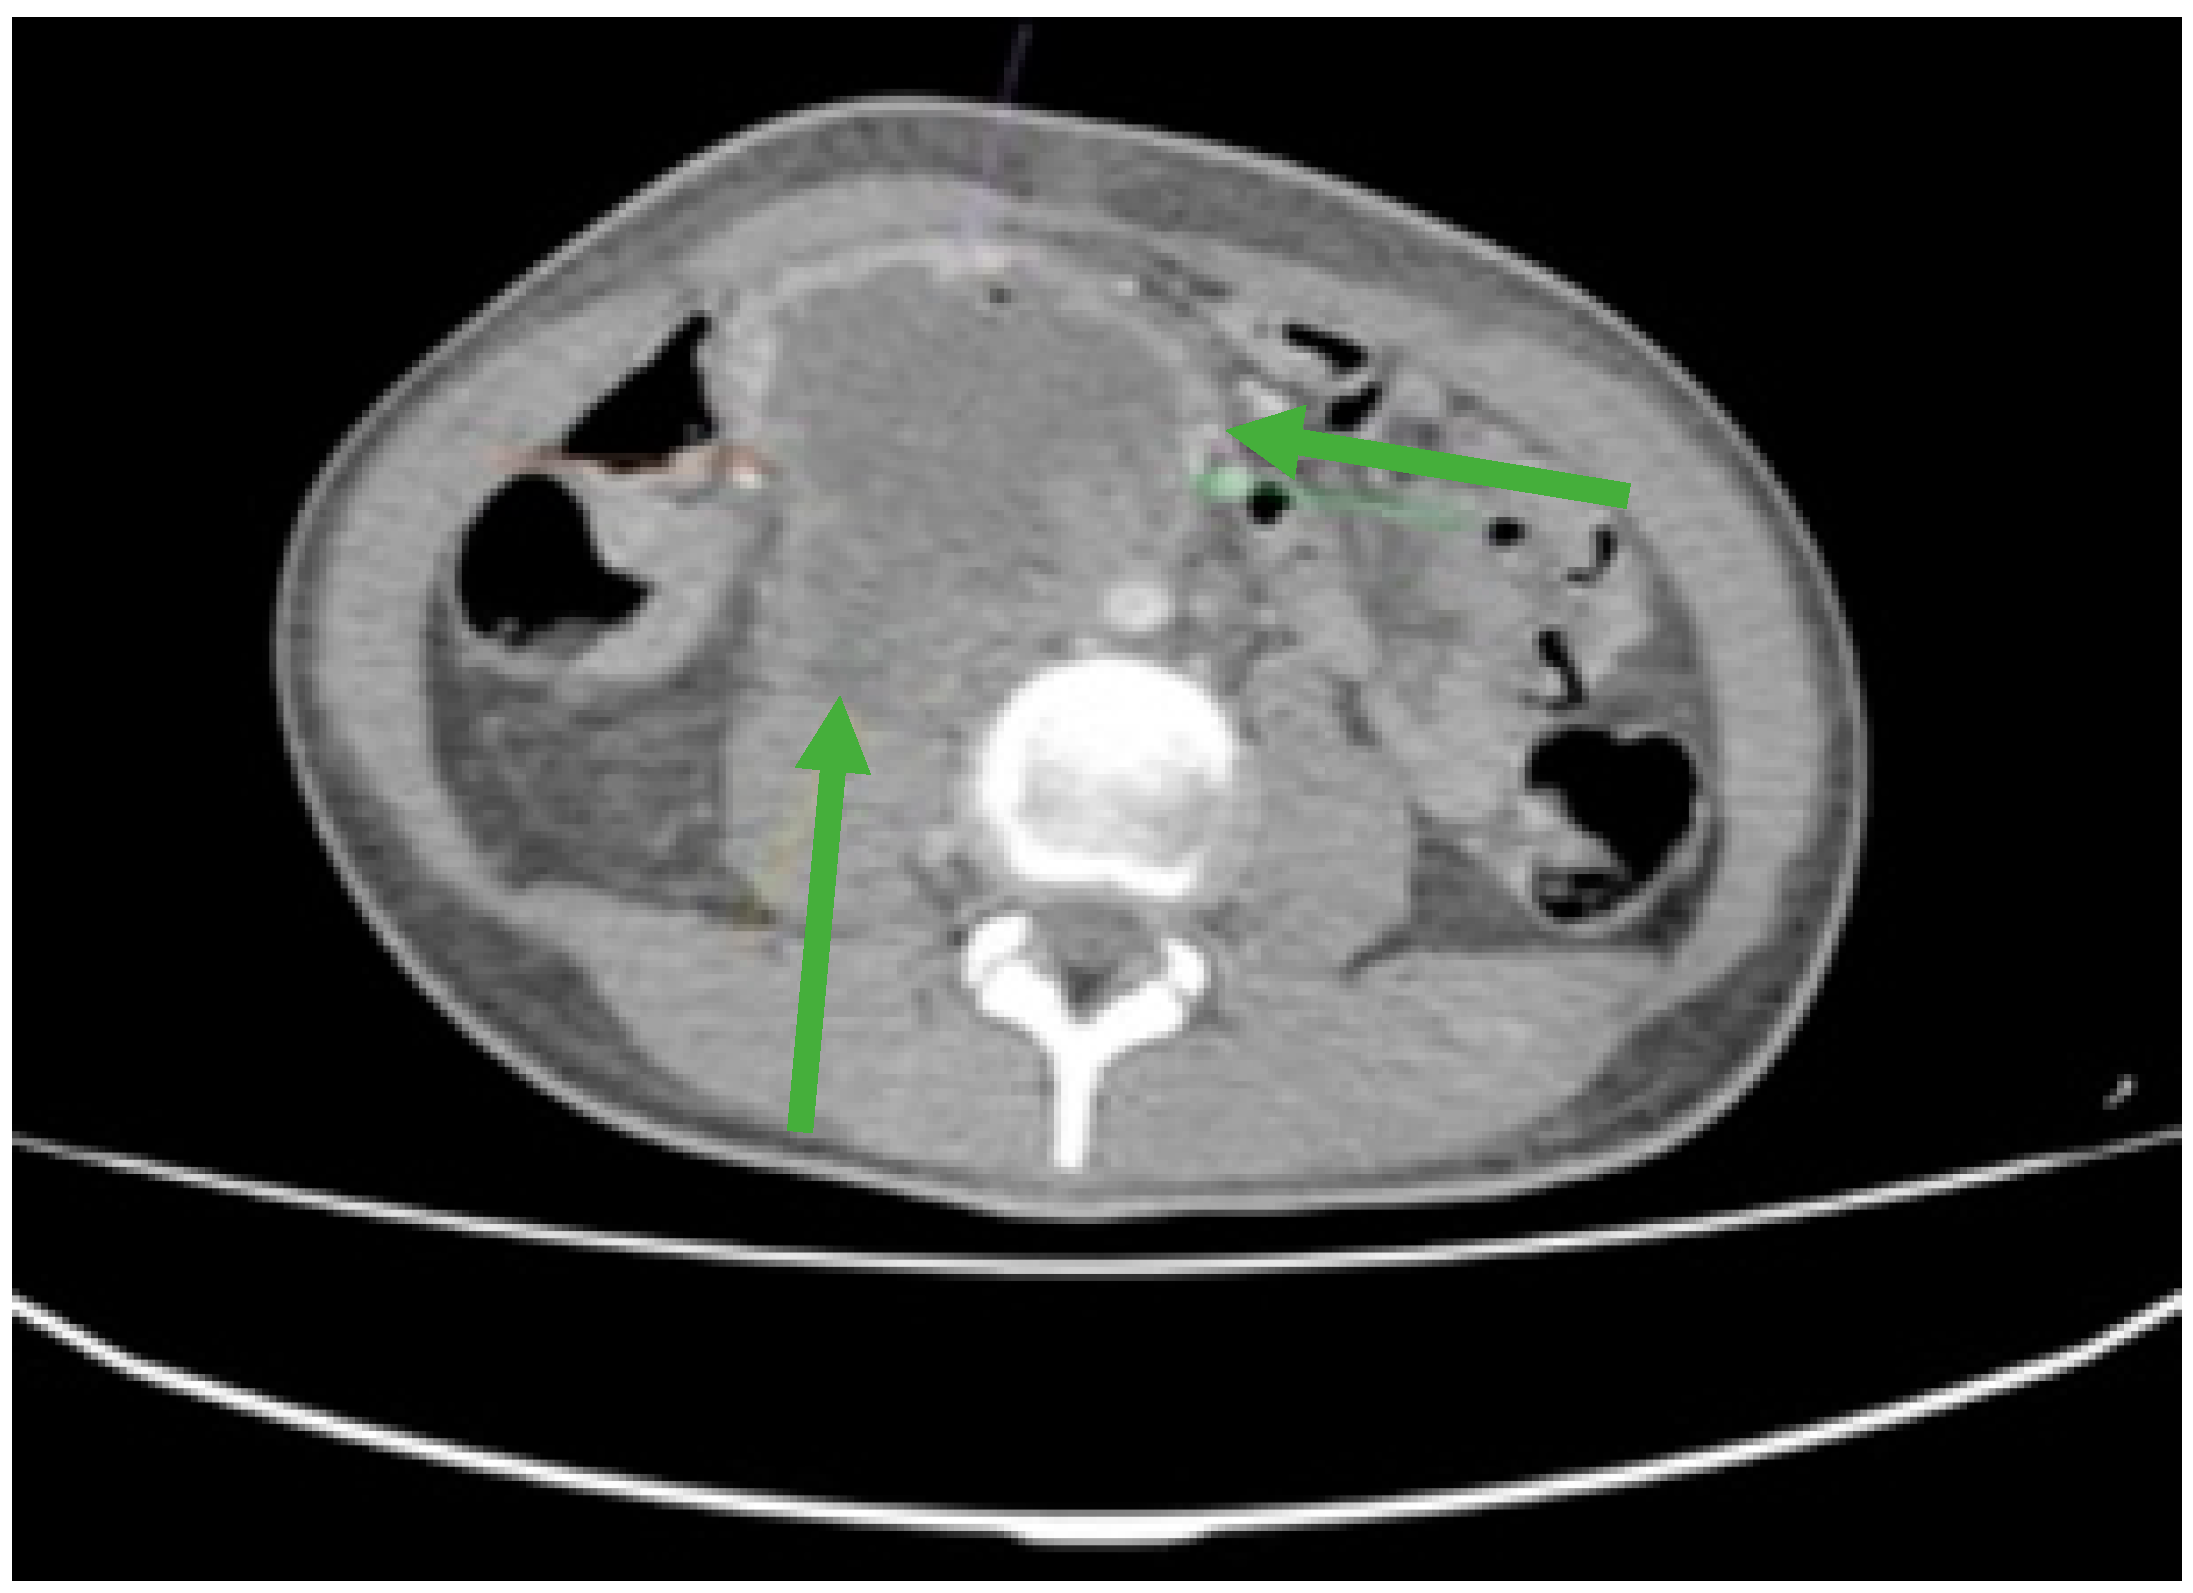

Figure 1.

Contrast-enhanced computed tomography (CT) revealed an irregular, slightly rounded retroperitoneal abdominal mass measuring 70 × 98 × 66 mm (green arrows).

Furthermore, laboratory investigations revealed severe anemia with a hemoglobin level as low as 4.2 g/dL. To gain a comprehensive understanding of the extent of the disease and its impact on the patient’s overall health, an extensive evaluation was conducted. This assessment included Endoscopic Retrograde Cholangiopancreatography (ERCP) and whole-body computed tomography (CT). These diagnostic tests collectively confirmed the presence of an extended retroperitoneal mass (Figure 1), which had invaded the duodenum, thus underscoring the severity and complexity of the patient’s condition.